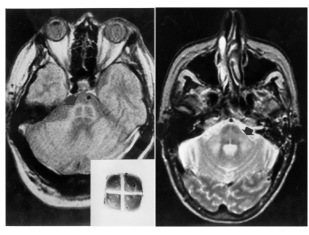

Hot cross bun sign refers to the cruciform-shaped hyperintensity on T2W axial magnetic resonance images (MRI) in multisystem atrophy (MSA), more commonly in MSA-C.

- It is called so because of its resemblance to Hot Cross Bun.(Sweet spiced bun baked by the Christian church on the last Thursday before Easter and marked with a cross on the top, with the four quarters representing the four quarters of the year. See the Images.

- The exact cause is not known but it is mostly due to selective loss of myelinated transverse pontocerebellar fibers and neurons in the pontine raphe and sparing of the pontine tegmentum and corticospinal tracts.

- Hot cross bun sign is a manifestation of pontine atrophy in MSA and is more commonly found in MSA-C.